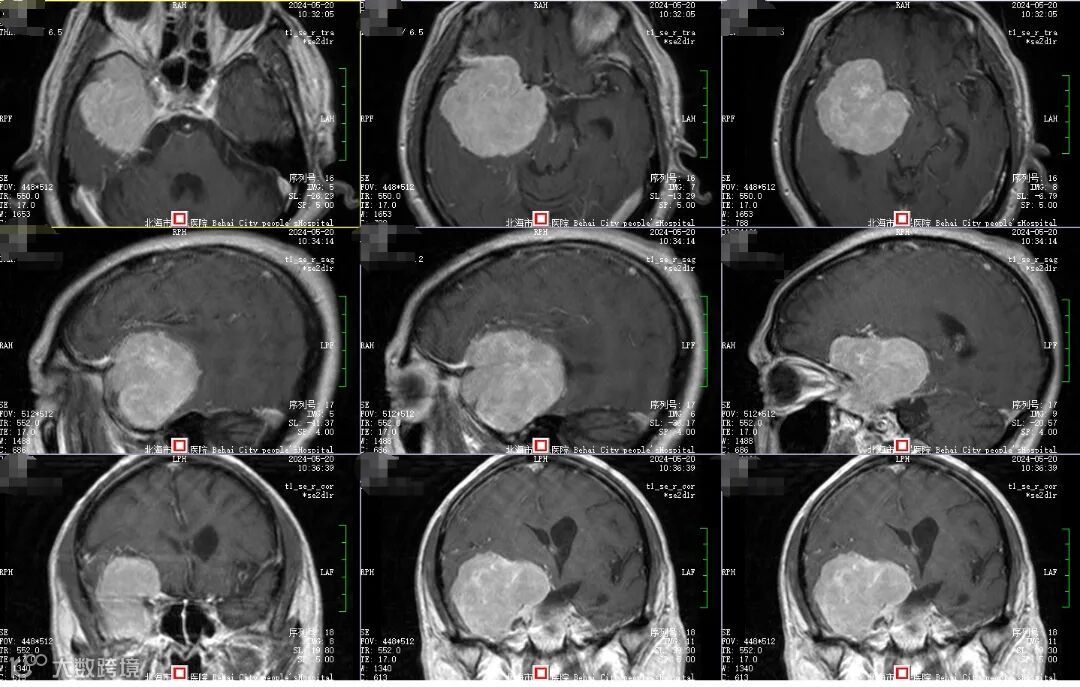

5月中旬,刘叔在家人陪同下来到市人民医院神经外科就诊,经CT检查发现“右额颞叶占位”,也就是说在刘叔脑部发现有一颗肿瘤,再次经过增强磁共振检查后,发现这是颗脑膜瘤长在了右额颞部蝶骨嵴上,大小约为59×61×58毫米。

5月下旬,在麻醉科、手术室以及助手莫贻敏的配合下,邓峰主刀手术为刘叔切除脑肿瘤,手术采用右侧翼点入路,在显微镜下进行分块切除。术中发现这颗肿瘤长的实在太大,还包绕了颈内动脉,附近神经受到压迫而移位。